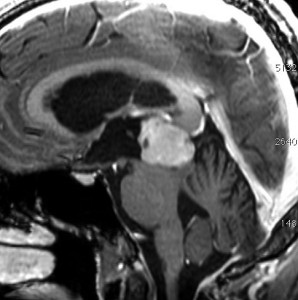

成人女性の松果体細胞腫で充実性腫瘍です。中脳水道が閉塞して軽度の水頭症(頭の中に髄液が溜まる)になってきています。多少凹凸がありますがだいたい楕円形。